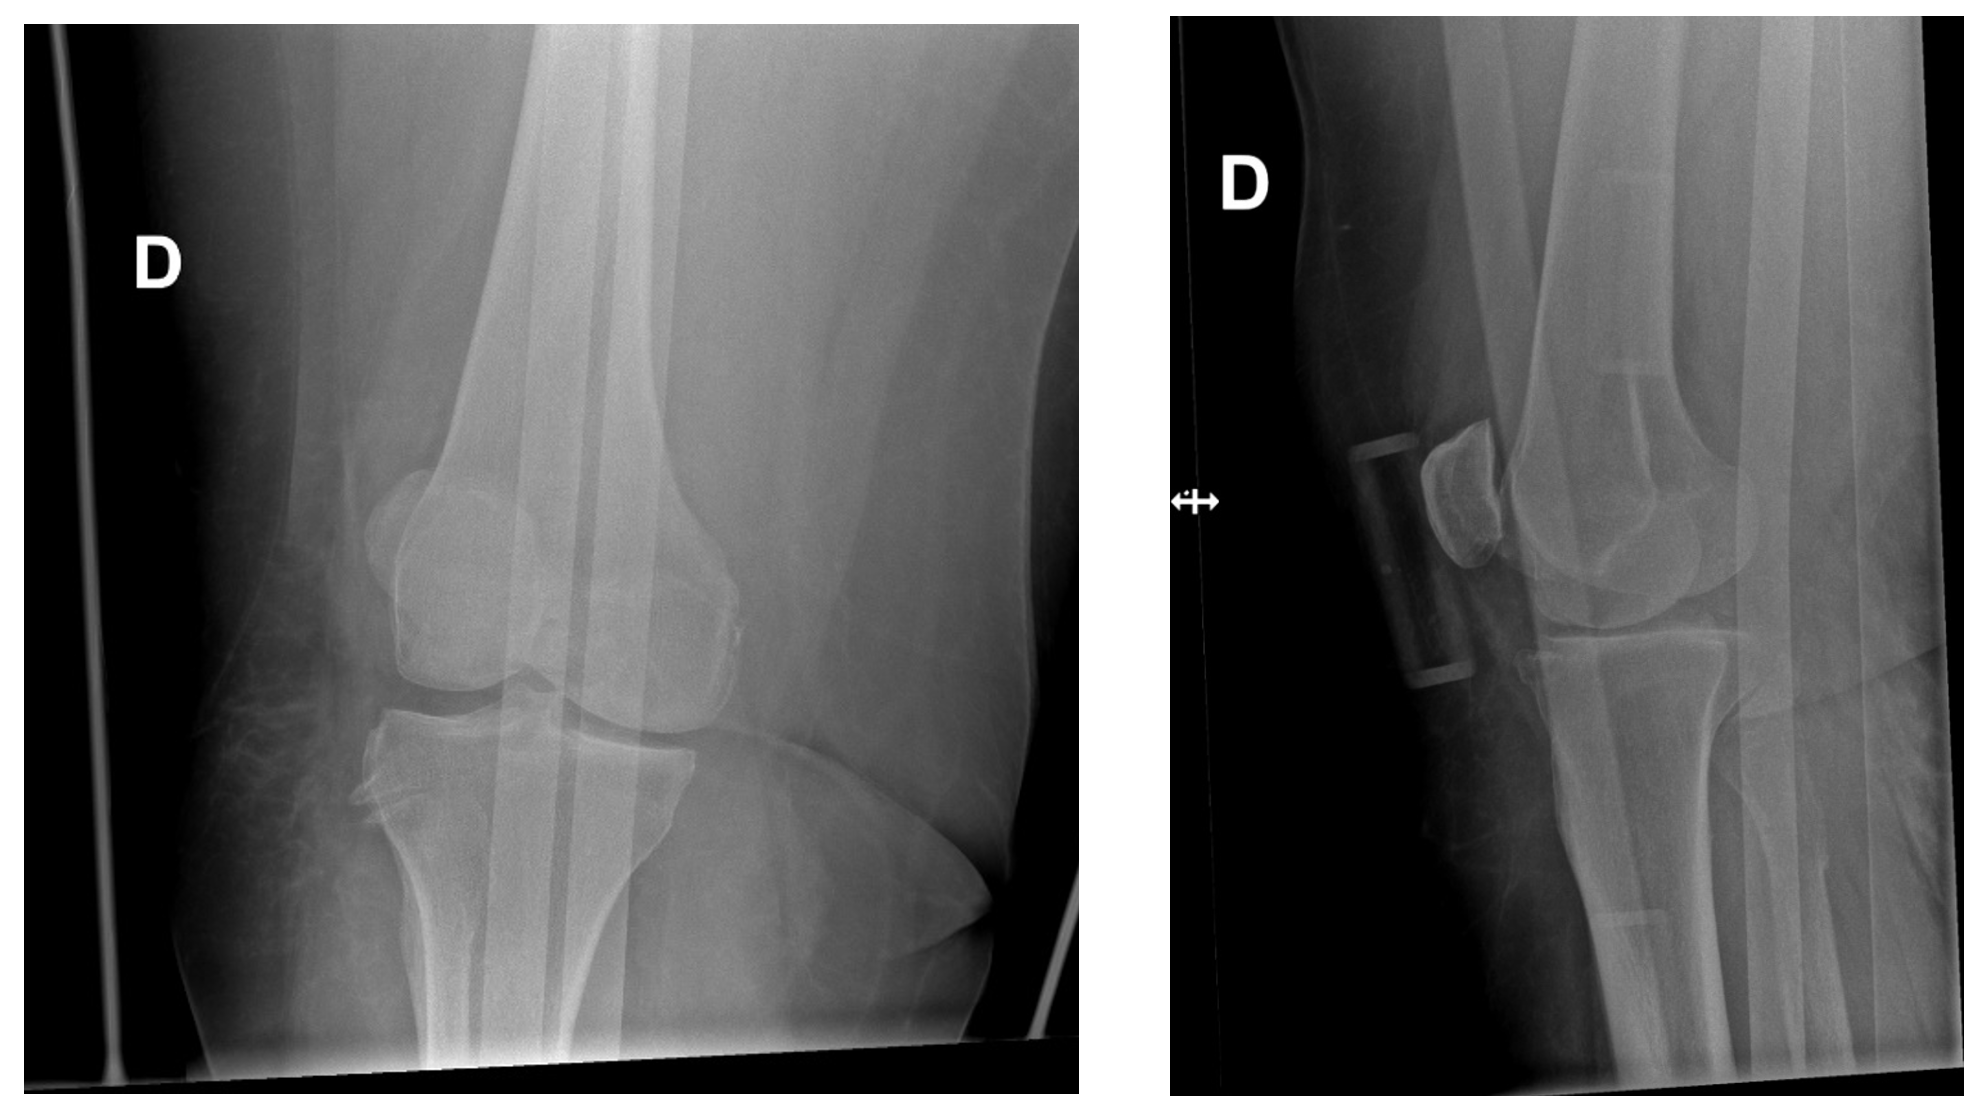

Les radiographies montrent une luxation antérieure du genou avant et après réduction.

La prises en charge consiste à effectuer rapidement une réduction fermée sous sédation-analgésie. A noter que les luxations postéro-latérales ne sont pas réductibles manuellement. Après réduction, il faut évaluer les pouls (palpés et au doppler) ainsi que le rétablissement de la congruence articulaire par de nouvelles radiographies. En cas d’absence de pouls ou d’asymétrie, un angio-CT sera effectué en urgence suivi d’une prise en charge par les spécialistes de chirurgie vasculaire. Il existe toujours des lésions ligamentaires en cas de luxation du genou. Un bilan par IRM permet de faire l’état des lieux des lésions méniscales et capsulo-ligamentaires et programmer la prise en charge orthopédique.